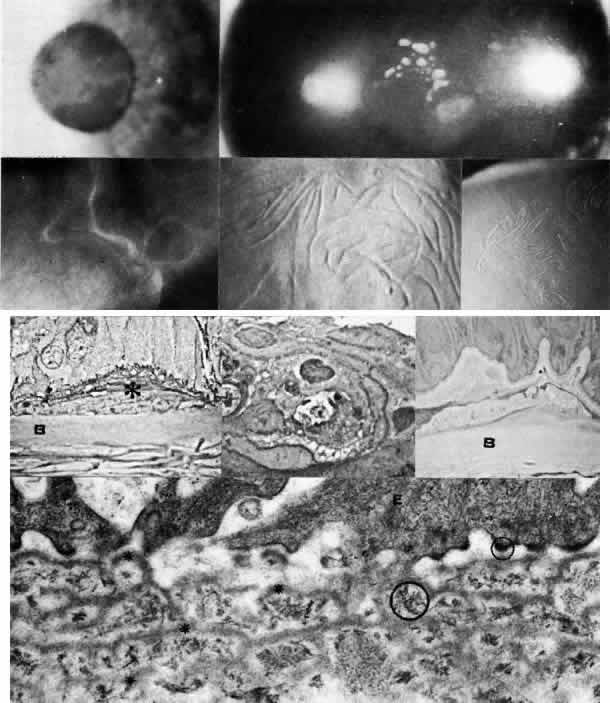

in Descemet's membrane. Arch Ophthalmol 79:123, 1968 196. Hogan MJ, Bietti G: Hereditary deep dystrophy of the cornea (polymorphous). Am J Ophthalmol 68:777, 1969 197. Boruchoff SA, Kuwabara T: Electron microscopy of posterior polymorphous degeneration. Am J Ophthalmol 72:879, 1971 198. Hanselmayer H: Zur Histopathologie der hinteren polymorphen Hornhautdystrophie

nach Schlichting. 1. Licht mikroskopische Befunde in Beziehung

zum Klinischen Bild, Graefes Arch Klin Ophthalmol 184:345, 1972 199. Hanselmayer H: Zur Histopathologie der hinteren polymorphen Hornhautdystrophie nach Schlichting: II. Ultrastrukturelle Befunde pathogenetische und pathophysiologische

Bemerkungen. Graefes Arch Klin Ophthalmol 185:53, 1972 200. Grayson M: The nature of hereditary deep polymorphous dystrophy of the cornea: Its

association with iris and anterior chamber dysgenesis. Trans Am Ophthalmol Soc 72:516, 1974 201. Tripathi RC, Casey TA, Wise G: Hereditary posterior polymorphous dystrophy: An ultrastructural and clinical

report. Trans Ophthalmol Soc UK 94:211, 1974 202. Cibis GW, Krachmer JH, Phelps CD, Weingeist TA: Iridocorneal adhesions

in posterior polymorphous dystrophy. Trans Am Acad Ophthalmol Otolaryngol 81:OP770, 1976 203. Johnson BL, Brown SI: Posterior polymorphous dystrophy: A light and electron microscopic study. Br J Ophthalmol 62:89, 1978 204. Cibis GW, Tripathi RC: The differential diagnosis of Descemet's tear (Haab's striae) and

posterior polymorphous dystrophy bands: A clinicopathologic study. Ophthalmology 89:614, 1982 205. Brooks AMV, Grant G, Gillies WE: Differentiation of posterior polymorphous dystrophy from other posterior

corneal opacities by specular microscopy. Ophthalmology 96:1639, 1989 206. Hirst L, Waring GO: Clinical specular microscopy of posterior polymorphous endothelial dystrophy. Am J Ophthalmol 95:143, 1983 207. Boruchoff SA, Weiner MJ, Albert DM: Recurrence of posterior polymorphous corneal dystrophy after penetrating

keratoplasty. Am J 0phthalmol 109:323, 1990 208. Rodrigues MM, Phelps CD, Krachmer JH et al: Glaucoma due to endothelialization of the anterior chamber angle: A comparison